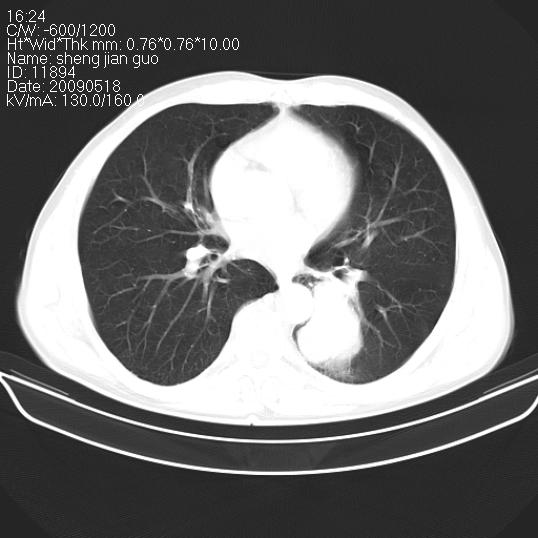

以下是引用zjzjr在2009-5-19 17:25:00的发言:[br]支持楼主考虑,另左肺下叶阻塞性炎症。

以下是引用zhao_bin2008在2009-5-19 17:48:00的发言:[br]支持左肺下叶周围型肺癌并阻塞性肺炎。

以下是引用zsl6918在2009-5-20 7:10:00的发言:[br]左侧中心型肺癌!